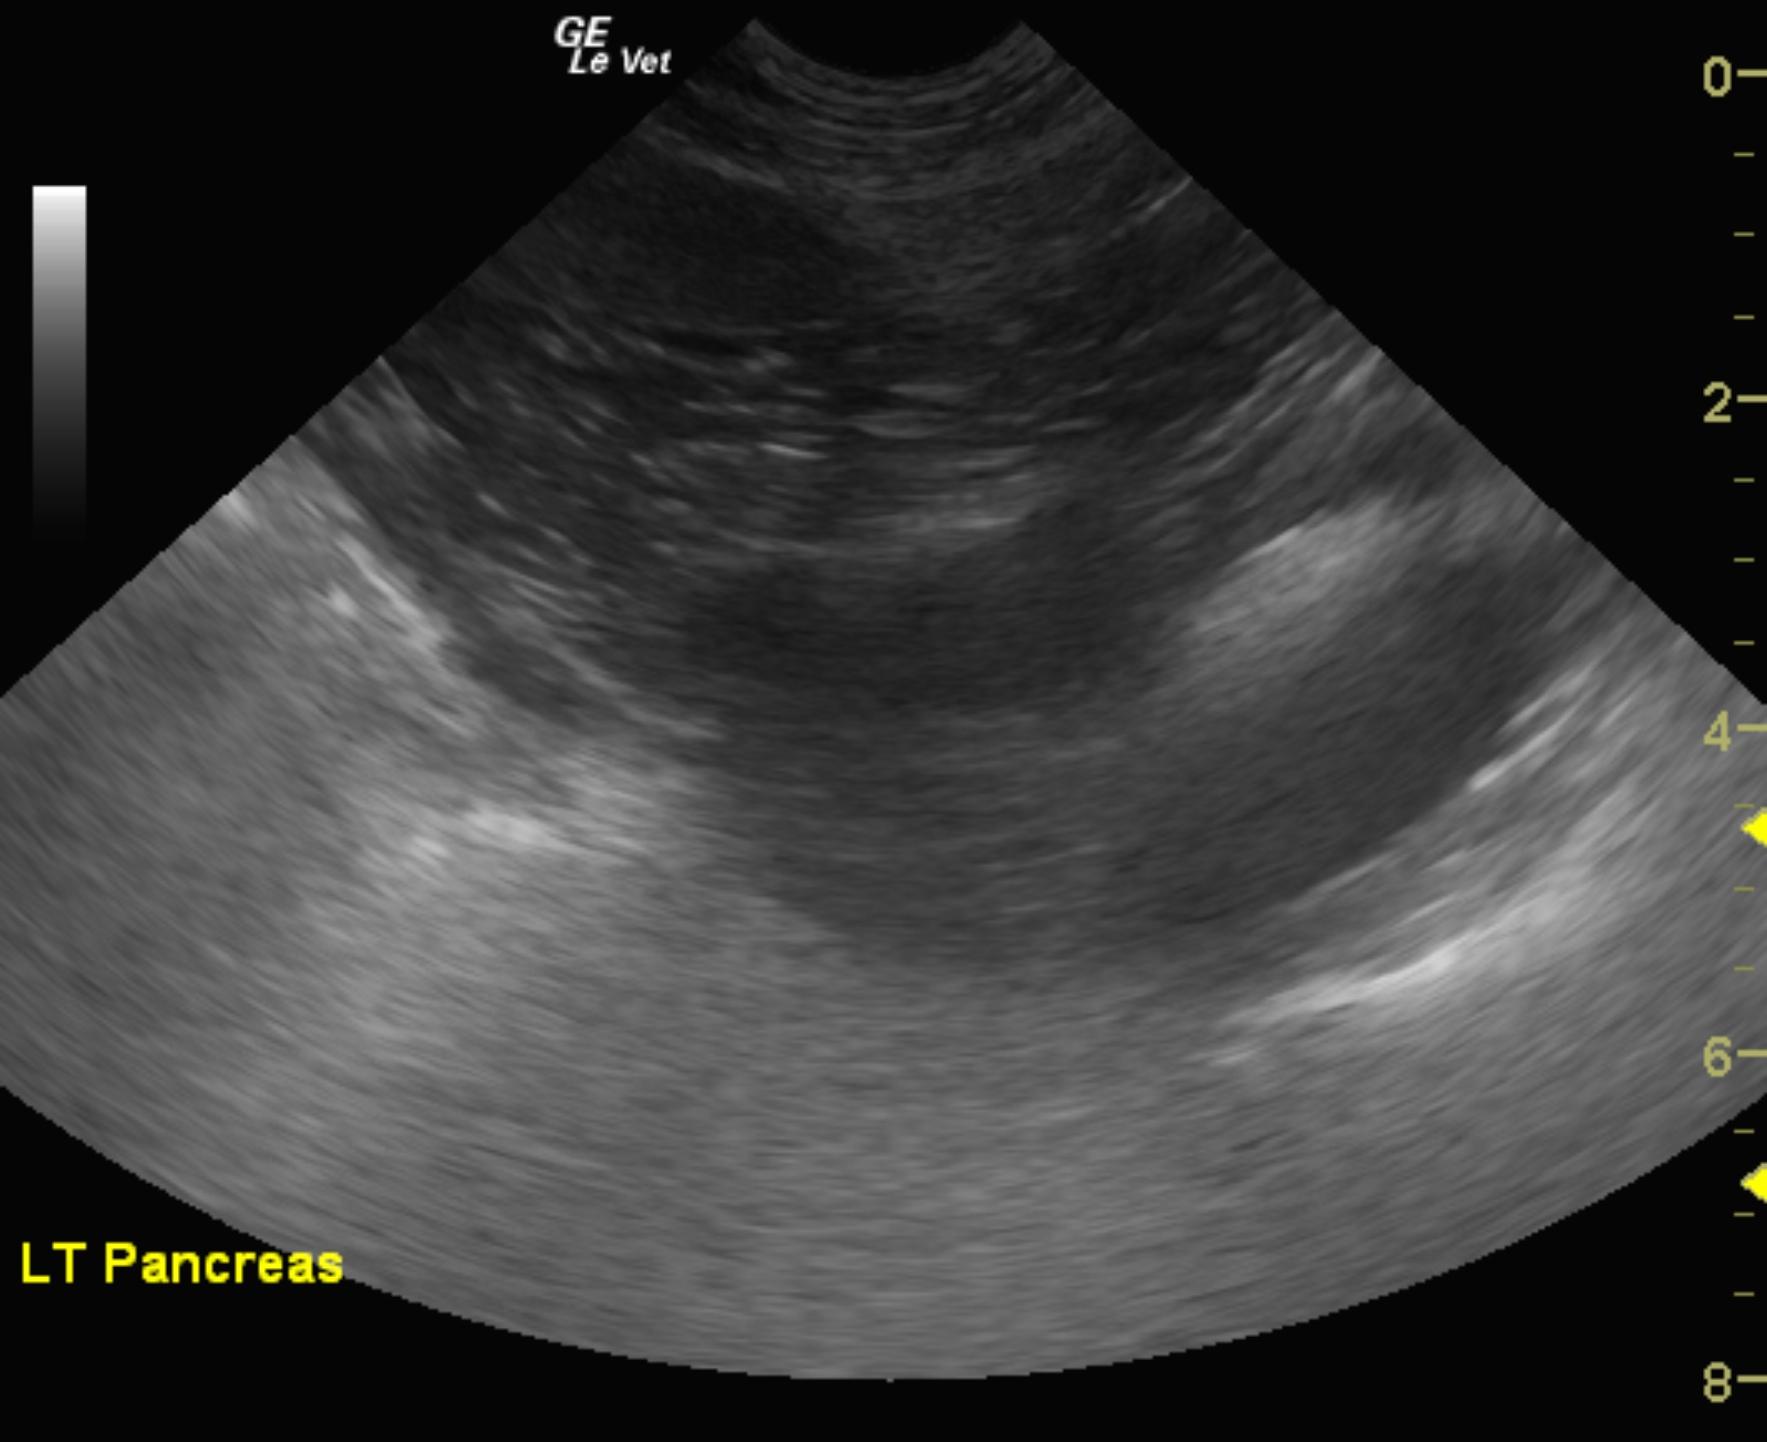

The left pancreatic limb revealed a 2 x 1.5 cm, hypoechoic nodule. The nodule was strongly vascular.

This is consistent with pancreatic nodule at the caudal pole of the left pancreatic limb or potentially a regional lymph node. This is strongly suspicious for metastatic or localized insulinoma. This lesion is adjacent to the mesenteric artery. Therefore, it very well may be a lymph node.